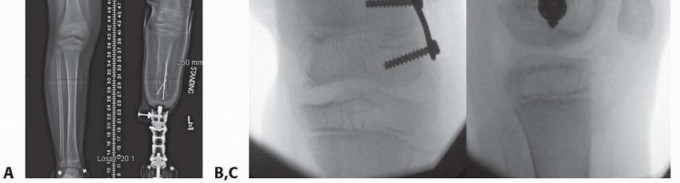

- ###

- FIG 3 • A. A 7-year-old boy with traumatic amputation from a lawn mower injury with varus deformity causing difficulty with prosthetic wear. B,C. Although the CORA was a result of fracture malunion proximal to the distal femoral physis, guided growth was chosen as an alternative to osteotomy to straighten the limb and to improve prosthetic wear.